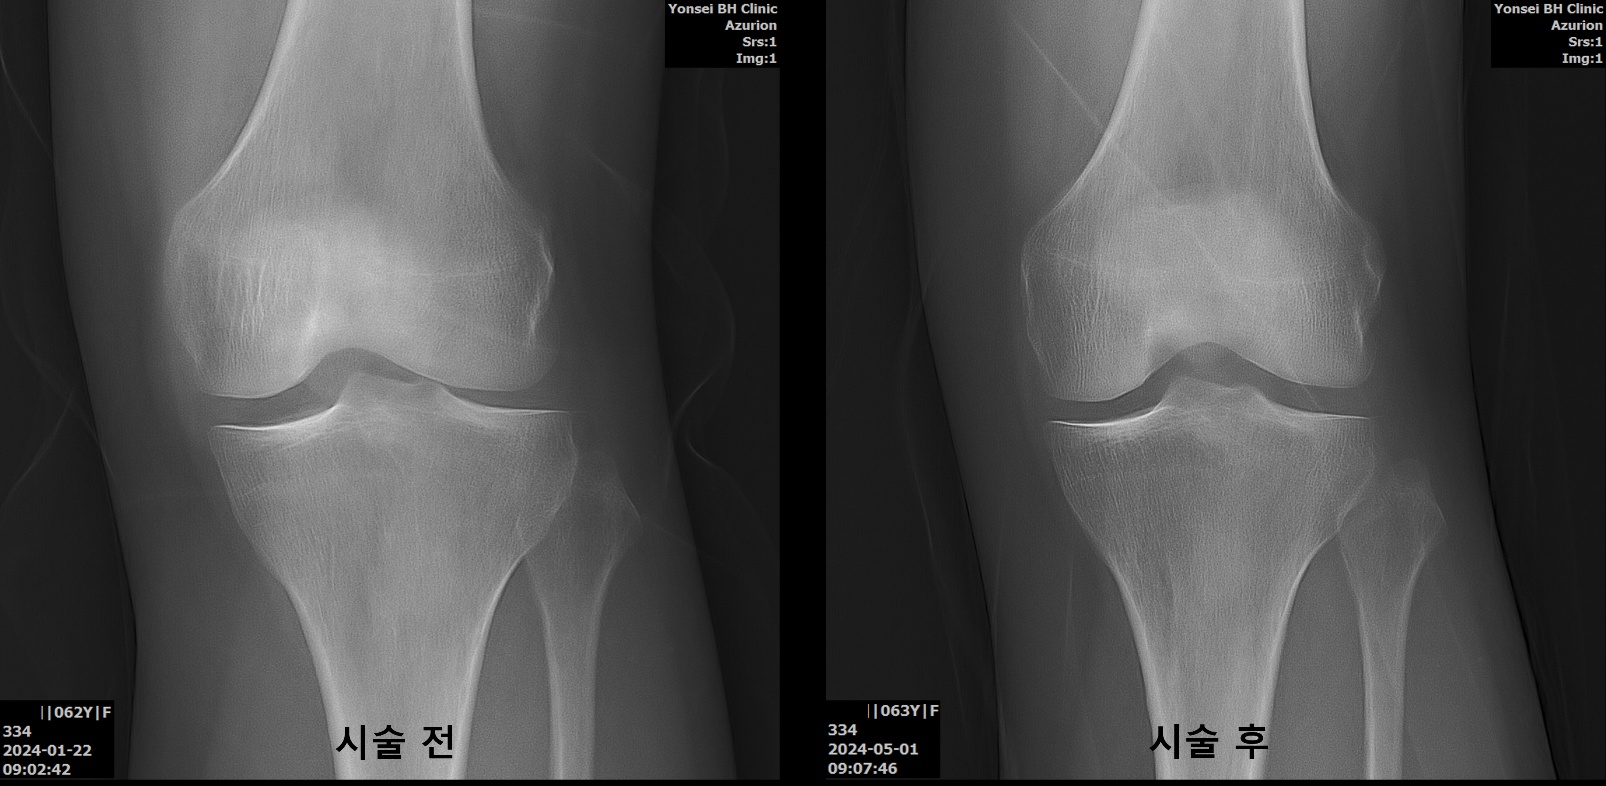

무릎 관절염 치료 시술 전후

무릎관절염 골수 줄기세포 시술 전후 63세 여성